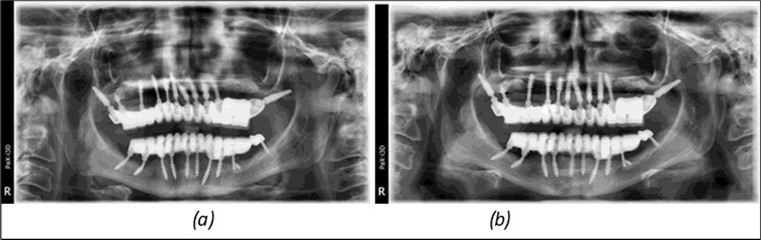

Figure 3.Panoramic pictures after removal of implants affected by peri-implantitis, extractions, alveolar crest regularization, and insertion of corticobasal and TPG implants (07.2022)

Figure 14.Rx panoramic final situation control: (a) Panoramic X-ray with the addition of a distal BCS implant in quadrant 3 at 11.2022; (b) Control X-ray, 10.2023.